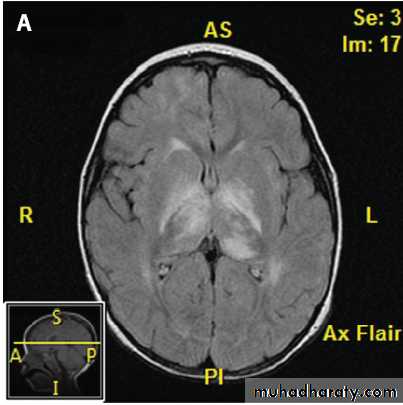

4- MRI brain normal or lesions not that area of ms like in area postrema of medulla ,hypothalamus …

--Clinically some manifestation mimic MS but associted with encephalopathy (confusion ,drowsiness)--MRI brain show demylinating plaques differ from that of MS plaques by it is larger, confluent, affect white and gray mater(basal ganglia and thalamus) and sotimes it is symetrical with contrast enhacement